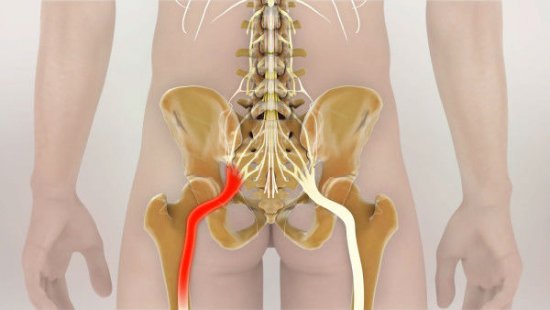

Еще один источник болей в пояснице – наличие межпозвонковых грыж. При их ущемлении, сдавливании нервных корешков возникает довольно сильная, резкая боль, справиться с которой на начальных стадиях помогают стероидные и нестероидные противовоспалительные препараты.

Грыжа позвоночника – частая причина боли

Признаком неблагоприятного исхода является люмбалгия, которая проявляется спектром разнообразных симптомов. Боли по ходу нервного корешка могут отдавать в ягодицы и ступни. Дискомфорт появляется при наклонах (даже при наклоне головы вниз), смехе, кашле и т. д. Болевой синдром усиливается при поднятии лежа на спине прямой ноги.

Симптоматика болей в спине носит разносторонний характер и зависит от имеющейся патологии. При растяжении боль проявляется в виде спазмов, движения при этом ограничены. Болевой синдром иррадиирует в ягодицы, заднюю часть бедер. Пациенту трудно наклоняться, совершать повороты корпуса. При повреждении корешков боли отдают в нижнюю часть тела, может быть нарушение чувствительности, онемение.